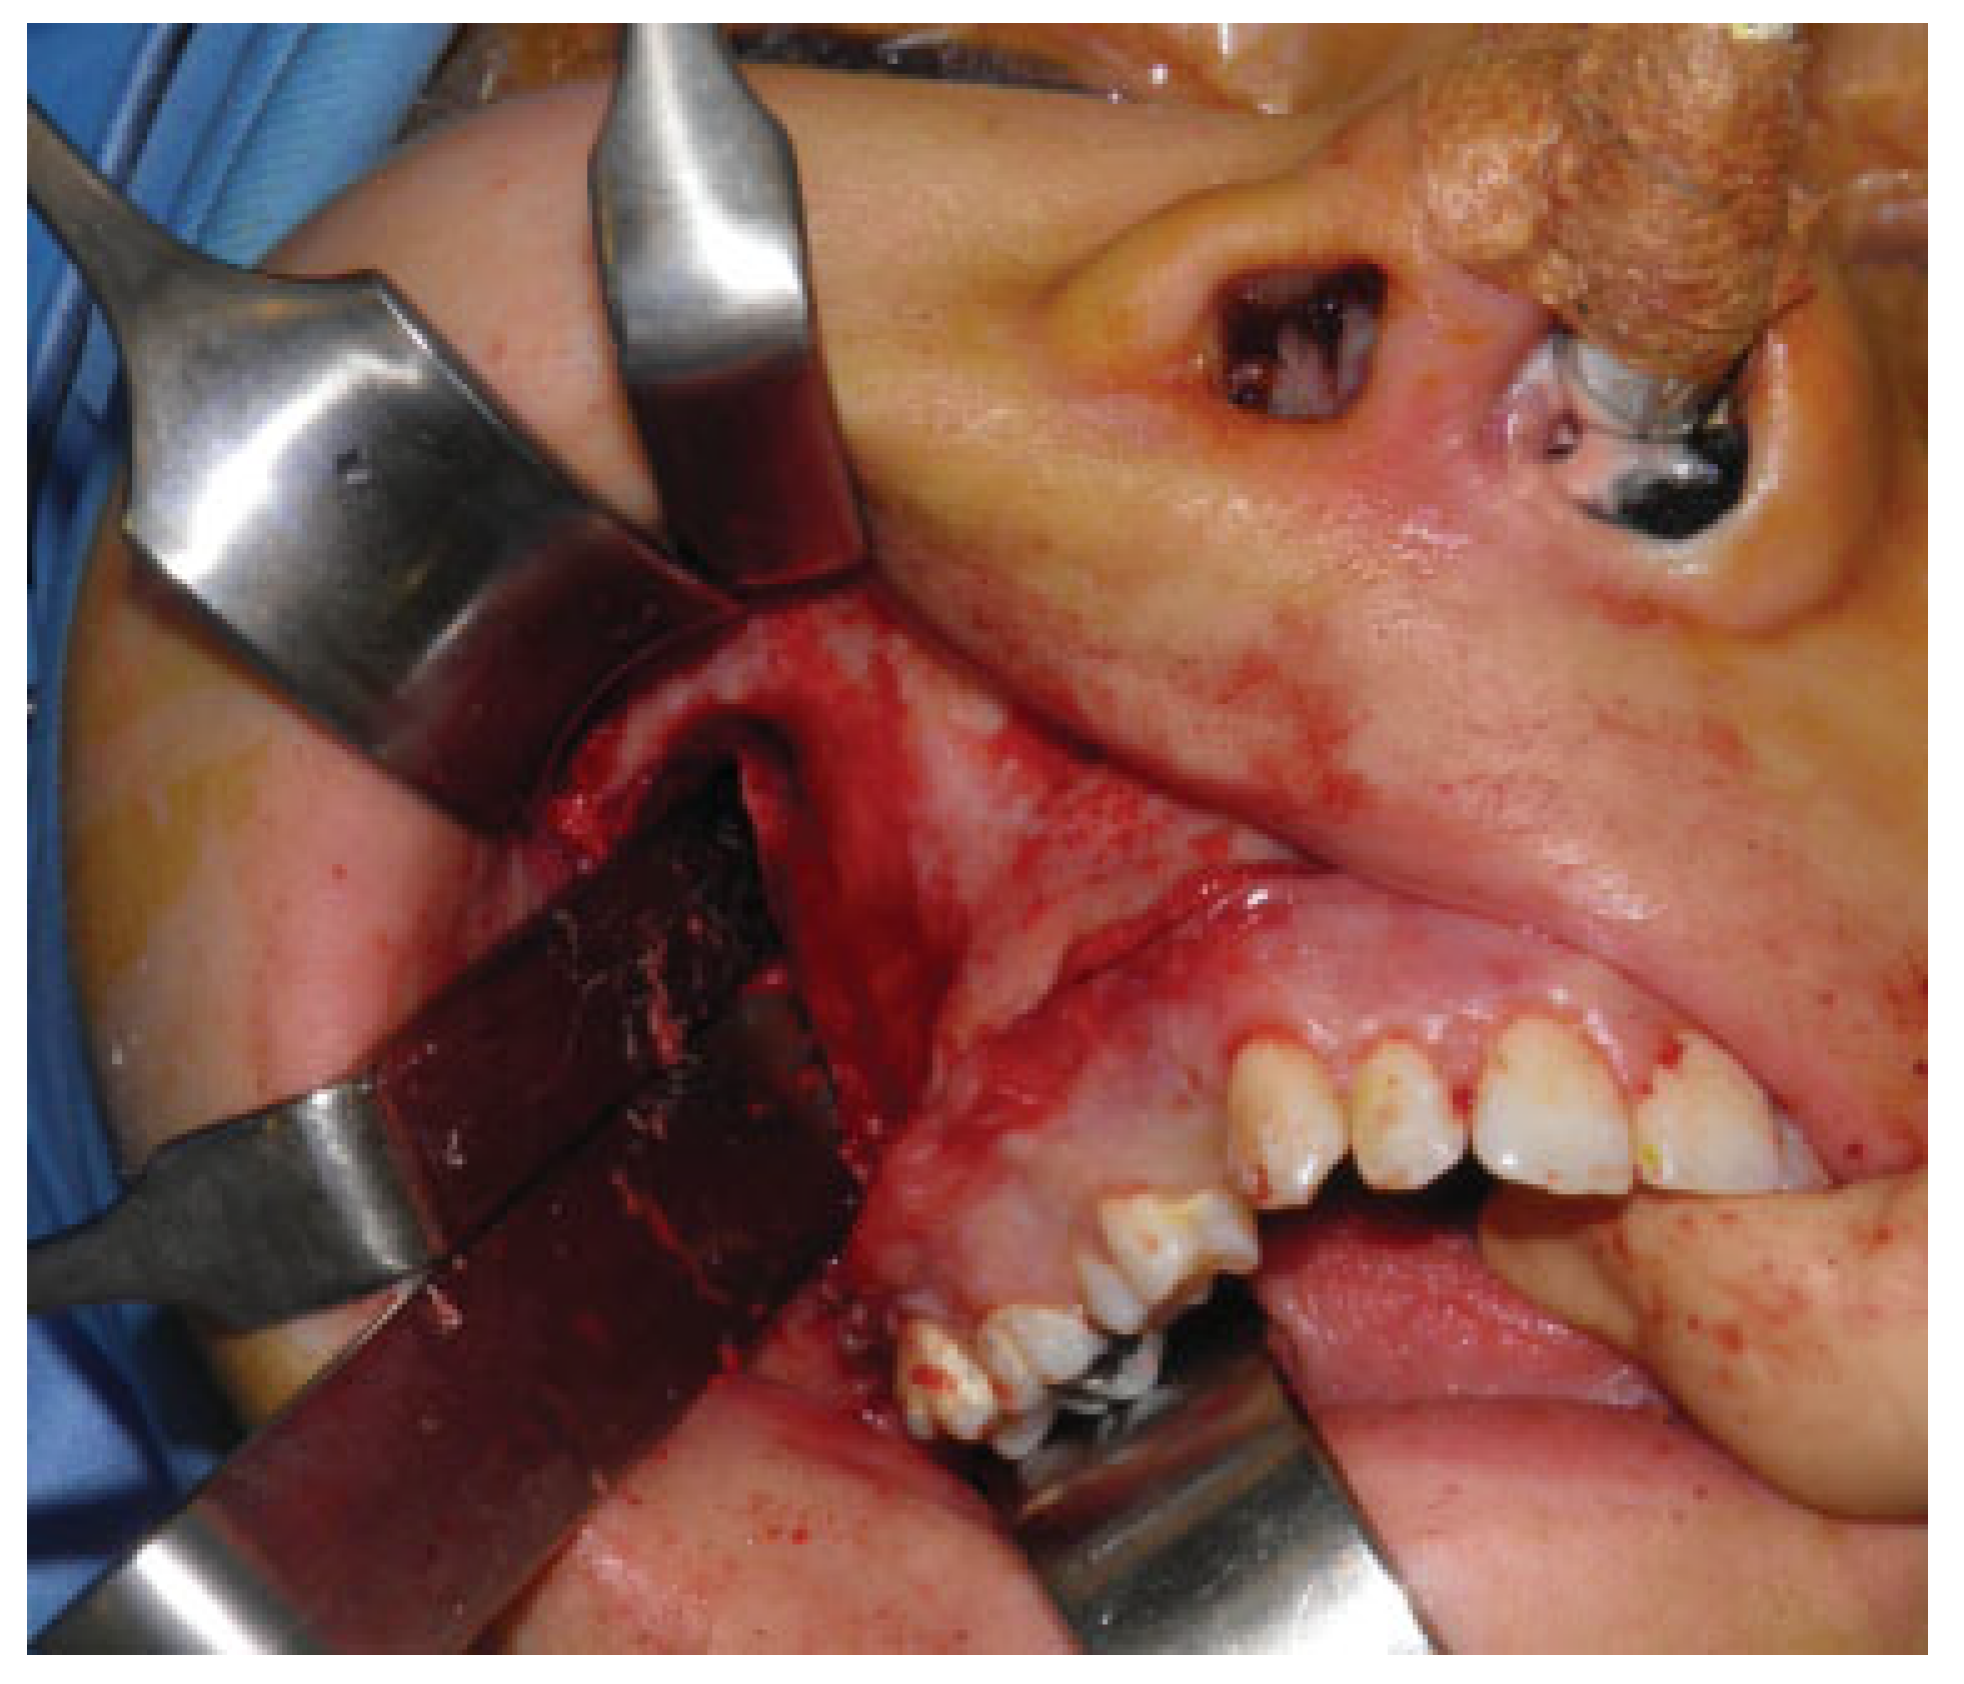

Segmental osteotomy, according to Schuchardt-Kufner, comprises the elements 1.5, 1.6, and 1.7; impaction of the maxilla 3 mm in the front and 10 mm in the rear with a feed rate of 4 mm; pterygomaxillary dysjunction; and mobilization of the bone fragment (Figure 3).

Figure 3. Segmental osteotomy according to Schuchardt-Kufner.